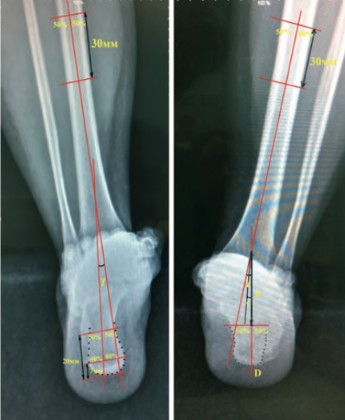

Любого доктора можно быстро подготовить как рентгенлаборанта и дать необходимые знания для оценки рентгенограмм.

Изучение проблемы низкого качества рентгенограмм на Вашем оборудовании.